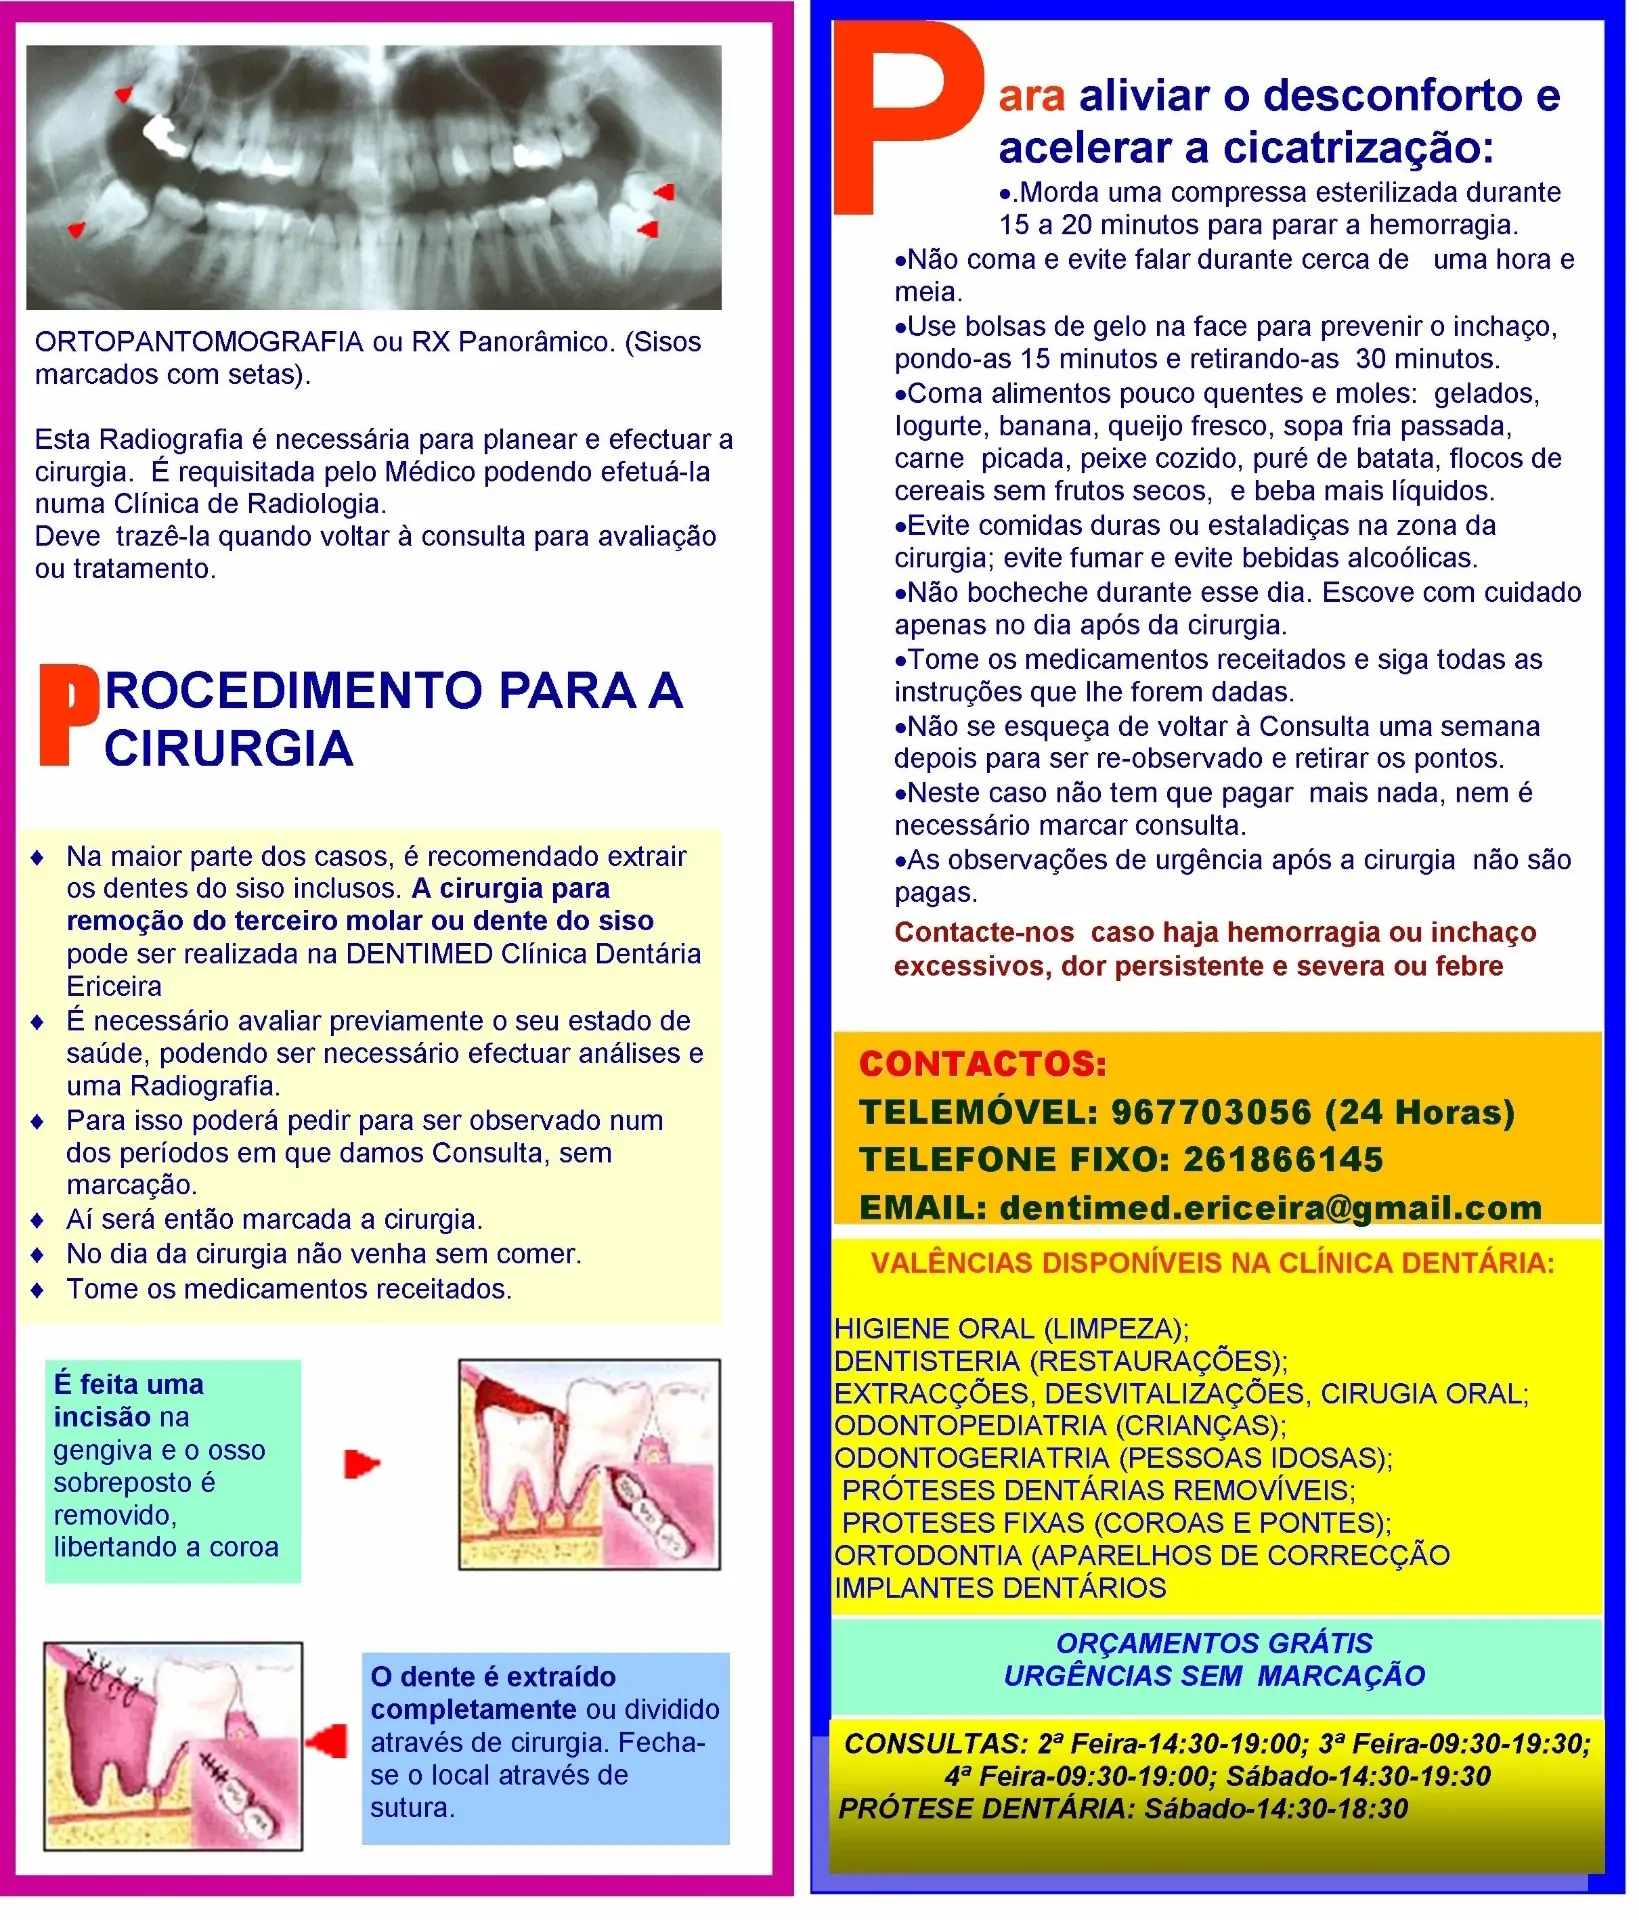

Extração de Sisos Inclusos

Os dentes do siso ou 3ºs molares são os últimos dentes a erupcionar ("nascer"). A maior parte de nós tem 4 dentes do siso, um em cada canto da boca (último dente). Normalmente desenvolvem-se no final da adolescência ou até aos 20 anos, podendo dar queixas mais tarde. Muitas vezes, os dentes do siso ficam presos ou encaixados no osso do maxilar em posições fora do normal, o que os impede de saírem de forma normal. Isto pode causar sobreposição ou deslocação de outros dentes ou levar ao desenvolvimento de cárie dentária ou doença da gengiva do dente à frente (segundo molar); dor acentuada sentida no ouvido, abcesso com inchaço da face e dificuldade em mastigar são frequentes. Na maior parte dos casos, é recomendado extrair os dentes do siso inclusos. A cirurgia para remoção do terceiro molar ou dente do siso pode ser realizada na DENTIMED Clínica Dentária Ericeira. É necessário avaliar previamente o seu estado de saúde, podendo ser necessário efectuar análises e uma Radiografia. Para isso poderá pedir para ser observado num dos Períodos em que damos Consulta, sem marcação. Aí será então marcada a cirurgia. No dia da cirurgia não venha sem comer. Tome os medicamentos receitados. Siga os outros conselhos que lhe forem dados.

Cuidados a ter após extração de dentes do Siso e cirurgias semelhantes

Para aliviar o desconforto e acelerar a cicatrização: Morda uma compressa esterilizada durante 15 a 20 minutos para parar a hemorragia. Não coma e evite falar durante cerca de uma hora e meia. Coma alimentos pouco quentes e moles: gelados, Iogurte, banana, queijo fresco, sopa fria passada, carne picada, peixe cozido, puré de batata, flocos de cereais sem frutos secos, e beba mais líquidos. Evite comidas duras ou estaladiças na zona da cirurgia; evite fumar e evite bebidas alcoólicas. Não bocheche durante esse dia. Escove com cuidado apenas no dia após da cirurgia.Tome os medicamentos receitados e siga todas as instruções que lhe forem dadas. Neste caso não tem que pagar mais nada, nem é necessário marcar consulta. As observações de urgência após a cirurgia não são pagas. Use bolsas de gelo na face para prevenir o inchaço, pondo-as 15 minutos e retirando-as 30 minutos. Não se esqueça de voltar à Consulta uma semana depois para ser re-observado e retirar os pontos.

- Contacte-nos caso haja hemorragia ou inchaço excessivos, dor persistente e severa ou febre